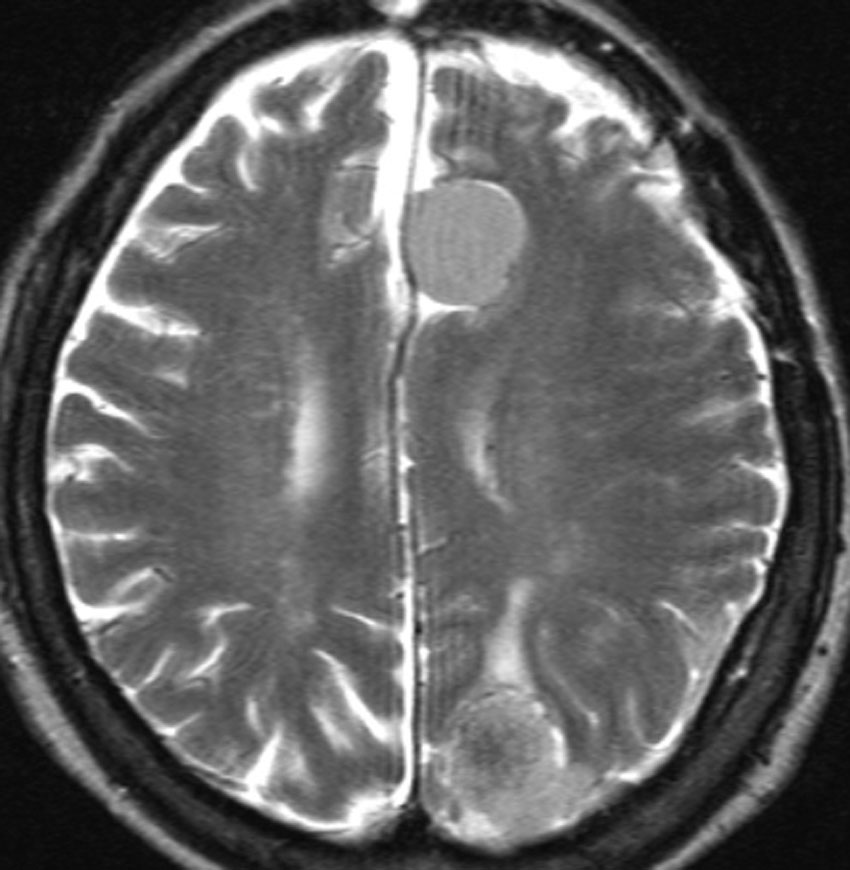

多発例,NF-2ではないもの

30代で下肢の局所てんかん発作で発見されました。テント上硬膜の腫瘍化です。数えれば総数で30個以上はあったでしょう。このタイプは手術で硬膜を広範囲切除(ほとんど全頭蓋冠)することで治すことができます。

H字状皮膚切開で広範囲両側前頭登頂開頭をして,穹窿部と傍矢状洞部髄膜腫をほとんど摘出してしまいました。上矢状洞は開存していたので残してあります。